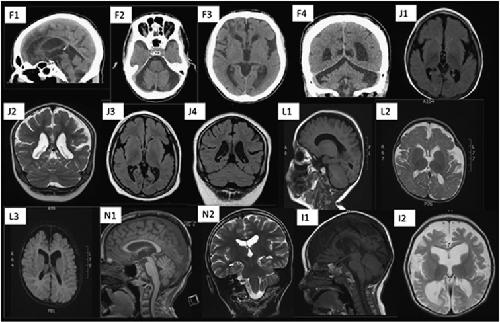

De novo mutations in FBRSL1 cause a novel recognizable malformation and intellectual disability syndrome.,

Ufartes R,Berger H,Till K,Salinas G,Sturm M,Altmüller J,Nürnberg P,Thiele H,Funke R,Apeshiotis N,Langen H,Wollnik B,Borchers A,Pauli S,

Hum Genet. November 1, 2020; 139(11):1432-1203.